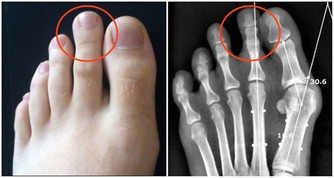

3. 貧血或營養不足

缺乏鐵質、維生素B群等營養素,可能導致貧血或血紅素不足,進而影響血液輸送氧氣的能力,導致身體末端供血不足,使手腳發冷。特別是飲食不均衡、挑食或長期節食減肥的人,更容易有手腳冰冷的問題。